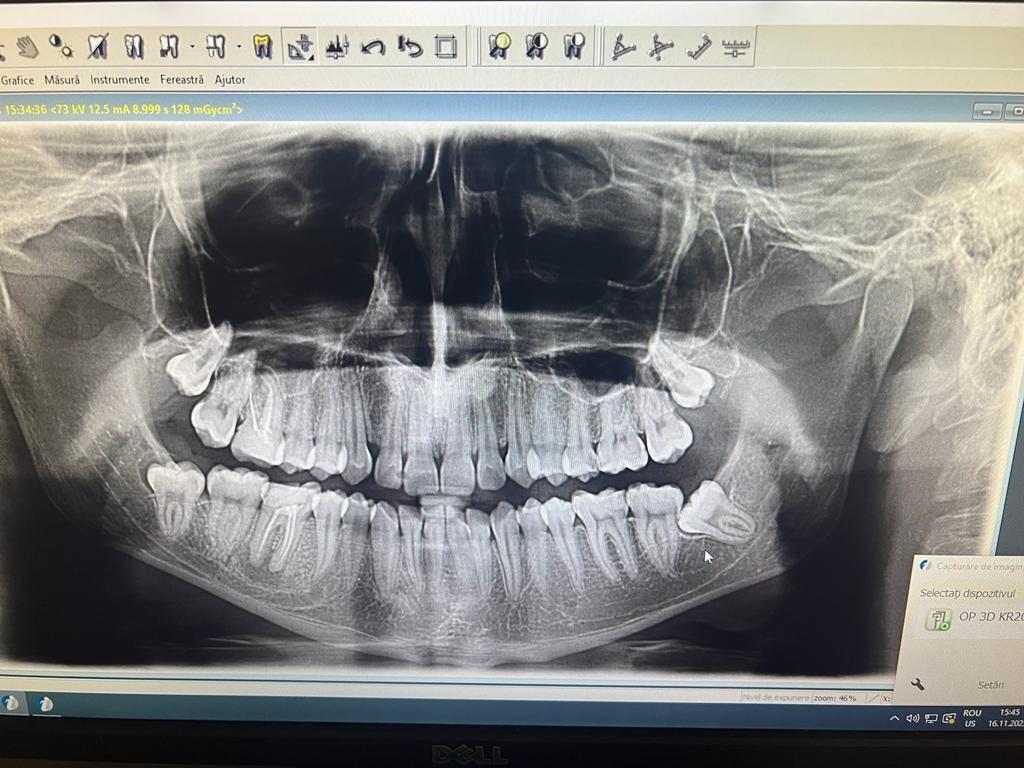

Stresul, fumatul, o igiena dentara precara, dar si modul de alimentatie duc la formarea cariilor. Acestea, netratate, favorizeaza aparitia infectiilor care vor dezvolta chisturi. Astfel de probleme se trateaza cu ajutorul tratamentului endodontic, zona respectiva fiind bine izolata pentru a preveni alte infectii. Atunci cand masurile nu sunt luate din timp, pulpa infectata moare si se formeaza chisturi la nivelul radacinii, iar interventia va deveni mai complexa.

Tratamentul endodontic este mult mai eficient si usor atunci cand bacteriile nu ajung pana in varful radacinii si nu apar chisturile.

– control radiologic.